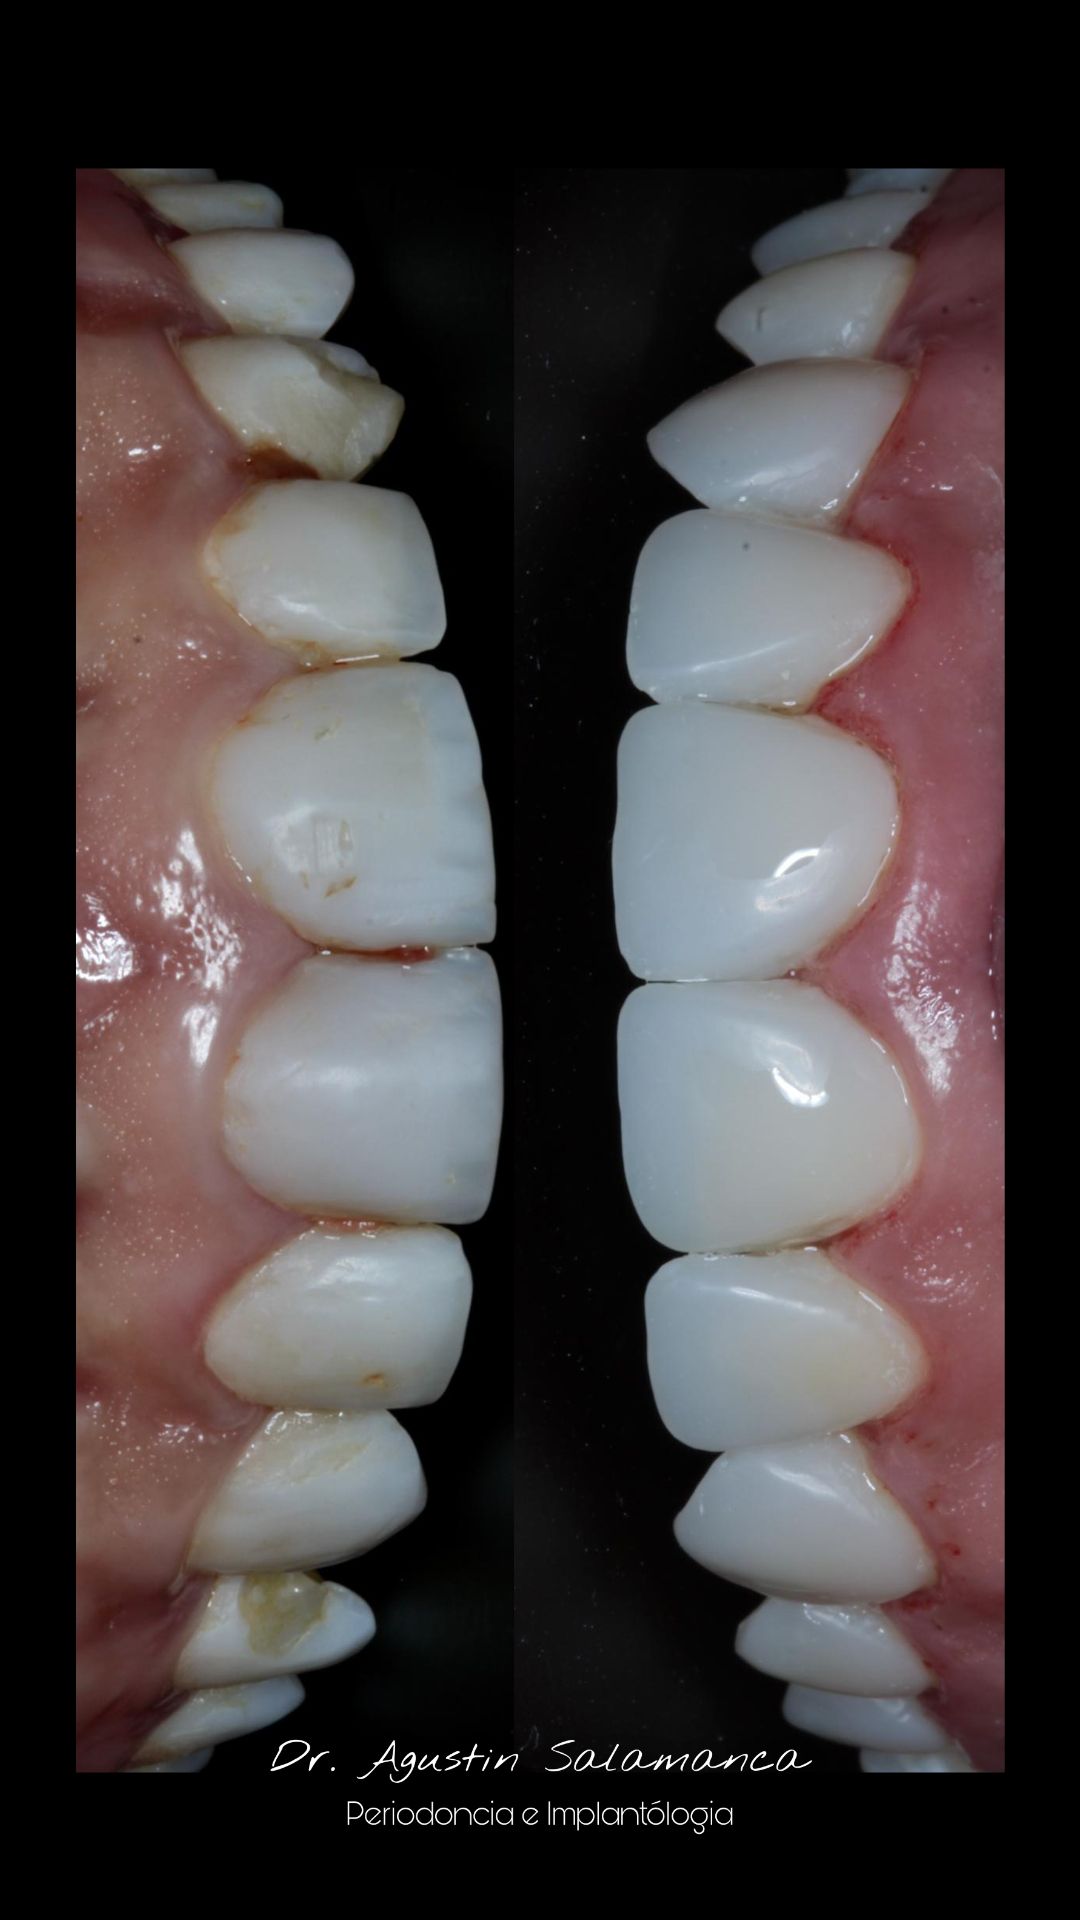

Fotos y videos

¿Que es un Implante Dental?

- Es un aditamento con forma de tornillo elaborado de titanio o de zirconio, que se inserta en el hueso a través de una pequeña cirugía, hasta que se osteointegre con el hueso y se coloque un provisional y posteriormente una corona definitiva.

-La ventaja de los Implantes Dentales es que sustituyen a los dientes o muelas perdidos sin que se tenga que desgastar los dientes adyacentes para un puente fijo.